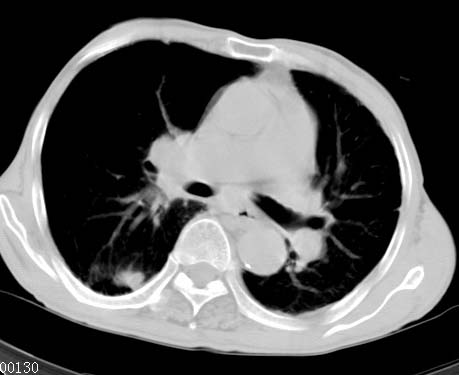

男性病人 81岁 胸痛 咳嗽2月 2周前提示右下肺感染.

今片ct示双肺多发结节影 可以这样诊断吗?1\双肺感染性病变 结核待排.

2\双肺纤维硬结灶,左肺肺气肿.

3\肺间质纤维化,胸膜肥厚粘连.

纵隔左移双肺上叶纤维硬结,肺气肿,双侧斑痕肺大泡,双侧胸膜增厚并胸膜下陈旧性病灶,右肺下叶胸膜下小结节影,密度较淡,建议复查.

病人桶状胸,胸廓肌肉消瘦;两上肺均可见纤维条索灶,下肺外围胸膜下可见间质纤维化改变,右下肺沿肺纹理分部结节样病灶,边缘光滑,考虑1、慢支并局灶性间质纤维化、右下肺合并感染,2、两上肺为陈旧性肺结核灶并瘢痕旁型肺气肿3、右下肺转移瘤待排。

两肺上叶见多发索条状高密度影,右肺下叶见片状、结节状高密度影,两肺体积增大,胸膜下区见囊状低密度影、内有分隔结构。左肺下叶见网格影。两侧胸膜见增厚影。诊断:两肺继发性肺结核。慢性支气管炎合并感染。肺气肿。肺间质纤维化。胸膜增厚。